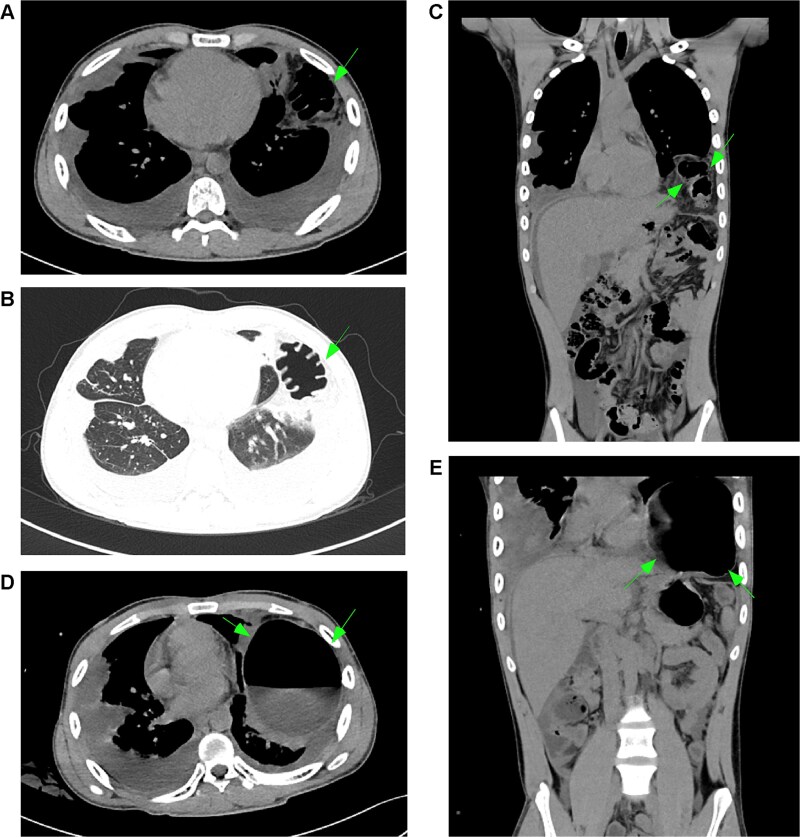

一例年轻男性Gorham-Stout综合征(GSS),一种罕见的导致骨质流失的淋巴血管疾病,表现为咳嗽、呼吸困难和乳糜胸膜积液感染金黄色葡萄球菌。尽管进行了胸导管结扎术,他的乳糜胸还是复发了。影像学显示胸骨和肋骨病变,胸膜增厚。肌电图显示轻度双侧膈神经运动传导异常。一年后,他出现了有症状的左侧膈疝并伴有部分肠梗阻,需要手术修复。本病例强调了GSS合并乳糜胸患者早期膈肌监测的必要性,以防止严重的并发症。

A young male with Gorham-Stout syndrome (GSS), a rare lymphovascular disorder causing bone loss, presented with cough, difficulty breathing, and chylous pleural effusion infected with Staphylococcus aureus. Despite thoracic duct ligation, his chylothorax recurred. Imaging showed bone lesions in the sternum and ribs, along with thickened pleura. Electromyography revealed mild bilateral phrenic nerve motor conduction abnormalities. A year later, he developed a symptomatic left diaphragmatic hernia with partial bowel obstruction that required surgical repair. This case highlights the need for early diaphragm monitoring in GSS patients with chylothorax to prevent serious complications.